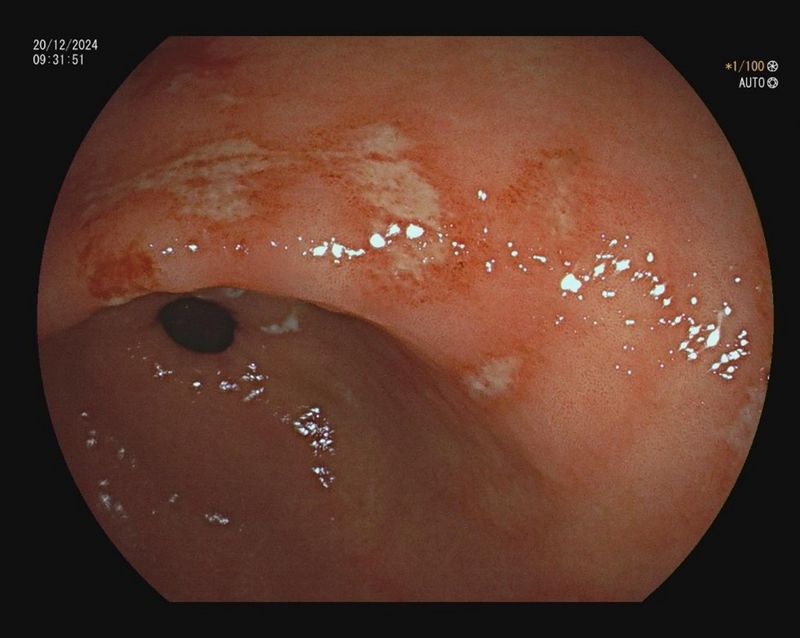

Resistenzgerechte Helicobacter-pylori-Eradikation und Antibiotic Stewardship

Endoskopische Ulcera sind u.a. eine Indikation für eine Helicobacter pylori Diagnostik. Im positiven Fall streben wir im Rahmen der Studie im Gegensatz zur Leitlinie keine empirische Therapie, sondern eine resistenzgerechte Therapie an.

Als Ursache abdomineller Krankheiten wird häufig eine Infektion mit H. pylori (HP) diagnostiziert. Eine sich daraus ableitende Eradikationstherapie erfolgt i.d.R. nach Leitlinie (LL) der DGVS 2022 mittels „Quadrupelschema“ (Pylera®), obwohl dieses u.a. auf Metronidazol basiert, worauf regional z.T. hohe Resistenzraten bekannt sind. Von der LL wird eine – grundsätzlich mögliche – Resistenzbestimmung erst nach ein- bzw. zweimaligem Therapieversagen vorgesehen.

Wir wollen dieses Vorgehen hinterfragen und stattdessen eine umfassendere Resistenzbestimmung zur resistenzgerechten antibiotischen Therapie vorschlagen.

Ziel der Studie ist eine umfangreiche Resistenztestung von Proben mit einem HP-positiven Urease Test für die Einleitung einer resistenzgerechten Therapie. Mit diesem Vorgehen lassen sich - so die Überlegung - Therapieversagen und eine damit verbundene erneute diagnostische Probeentnahme verhindern. Zusätzlich können wir regionale Resistenzdaten sammeln, Antibiotika sparen und die Resistenzentwicklung im Sinne von Antibiotic Stewardship positiv beeinflussen. Nähere Informationen sind im Deutschen Register für klinische Studien hinterlegt: https://drks.de/search/de/trial/DRKS00033330/details